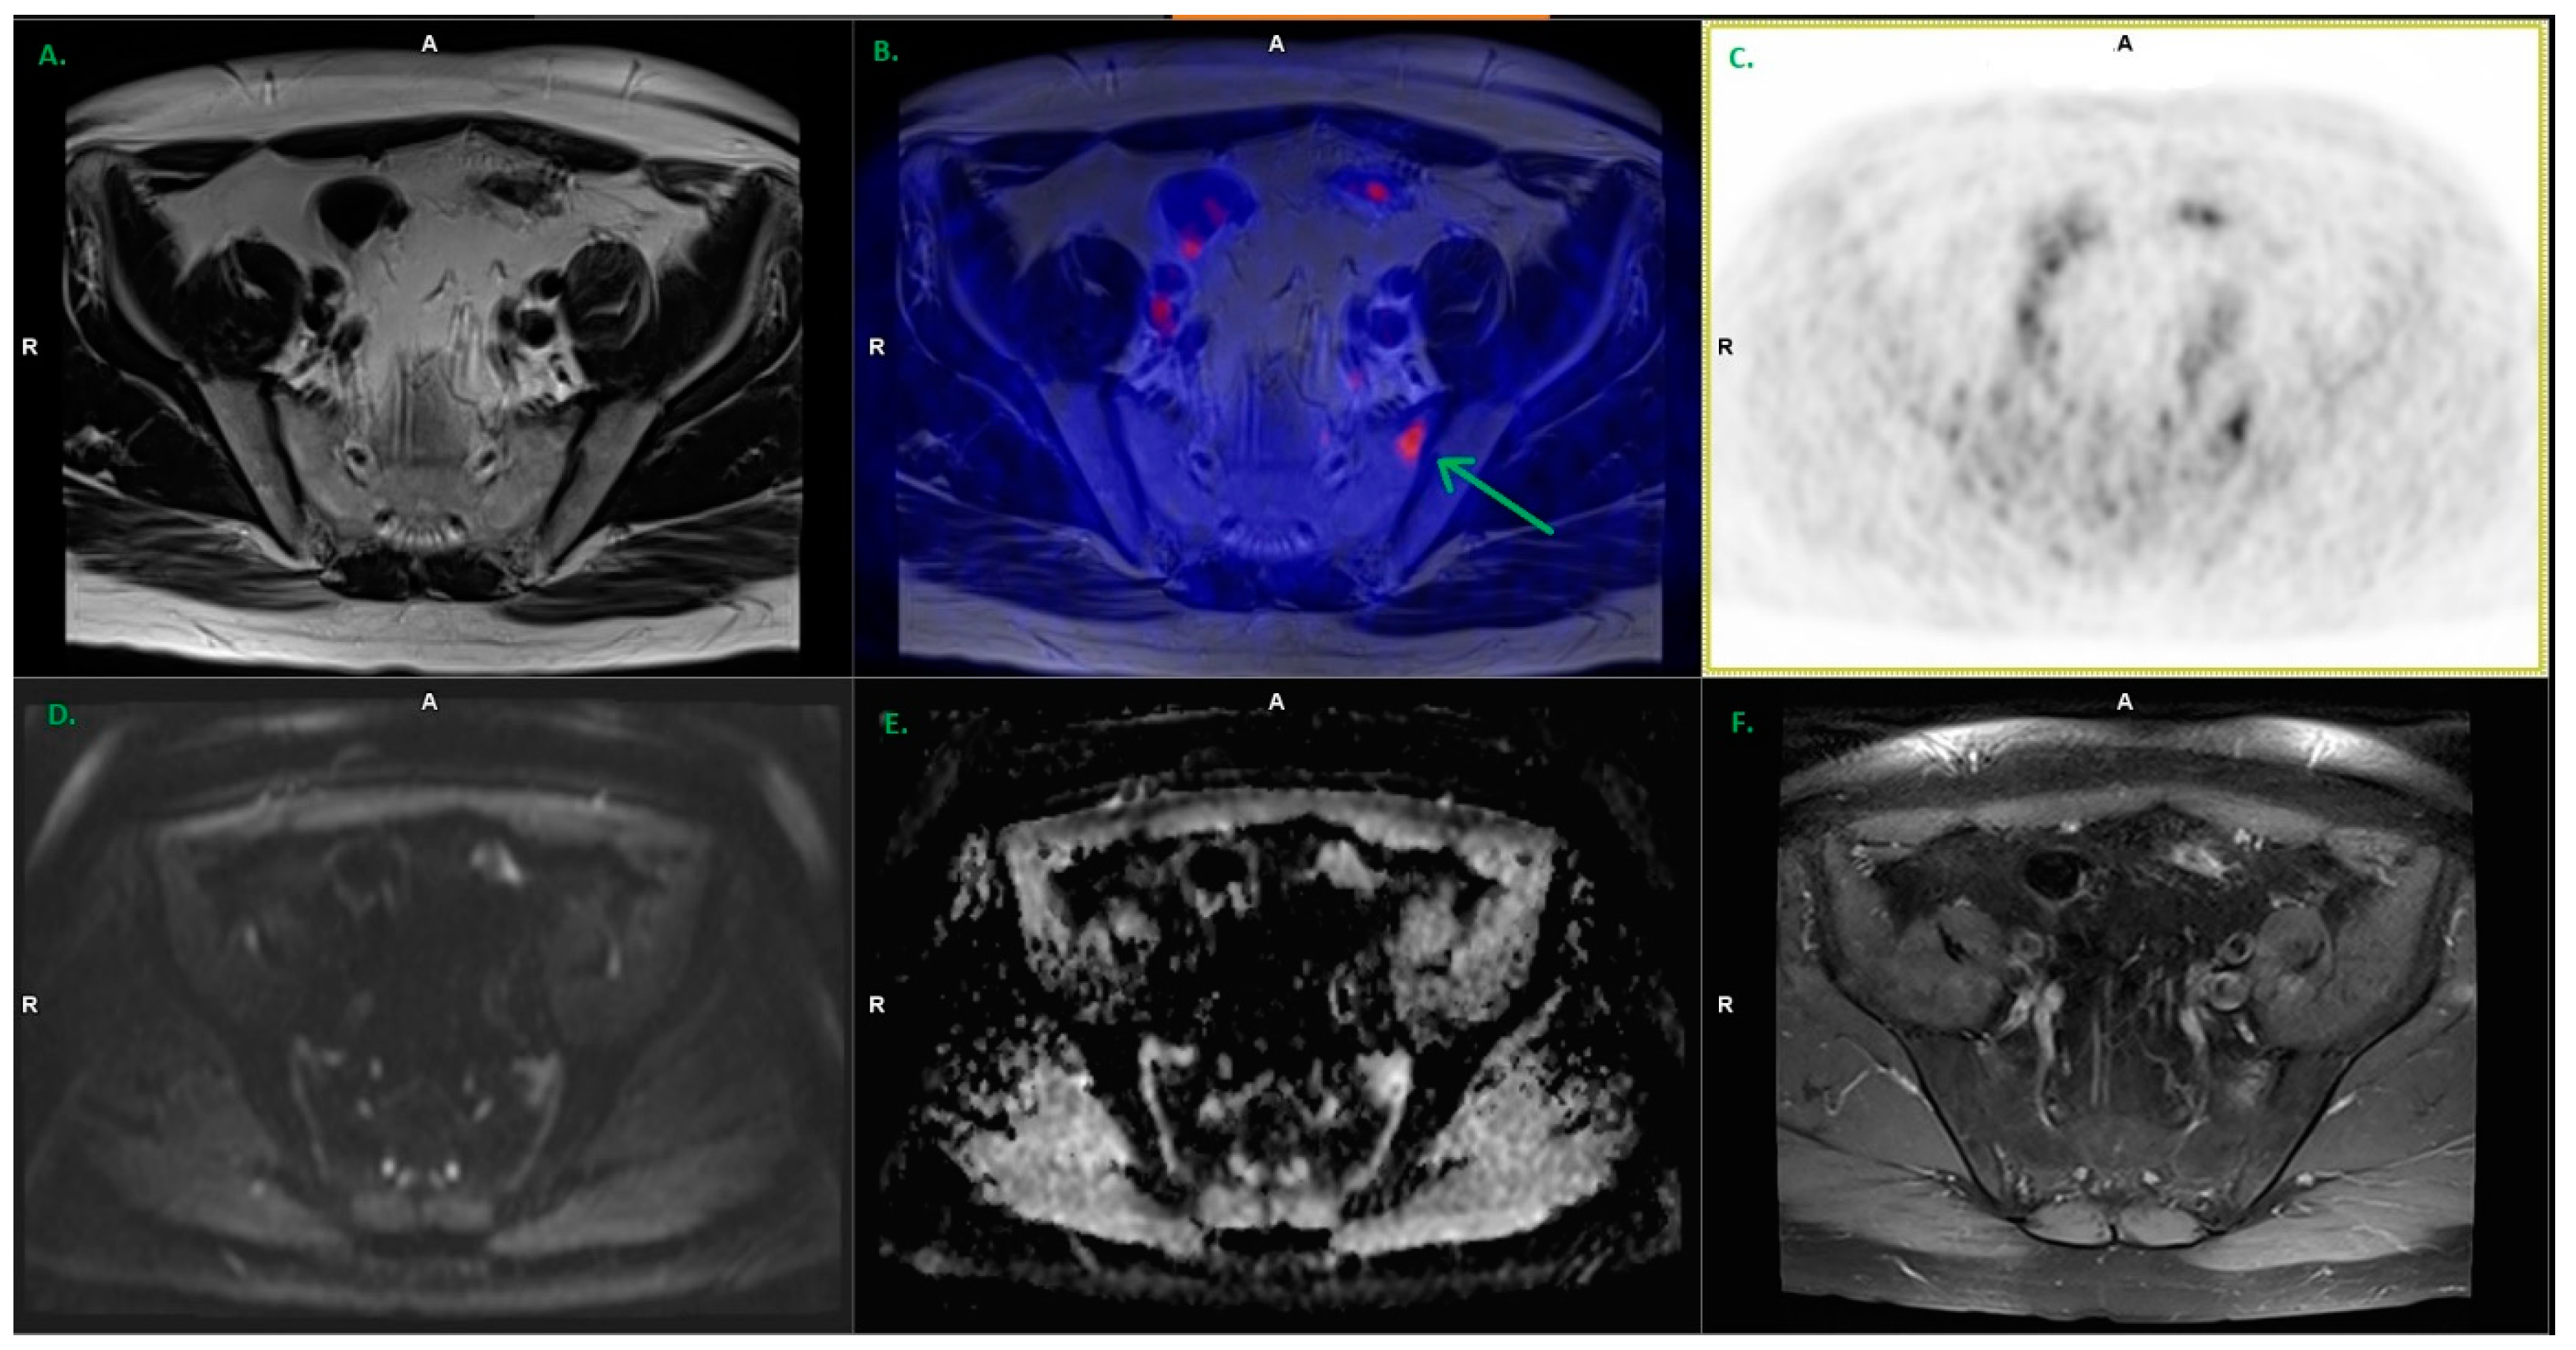

3.2. Lymph Nodes

| Pelvic lymph nodes | 34 | 5.46 ± 3.28 | 3 × 3 up to 11 × 11 |

| Extrapelvic lymph nodes | 1 * | 3.75 | 3 × 3 |